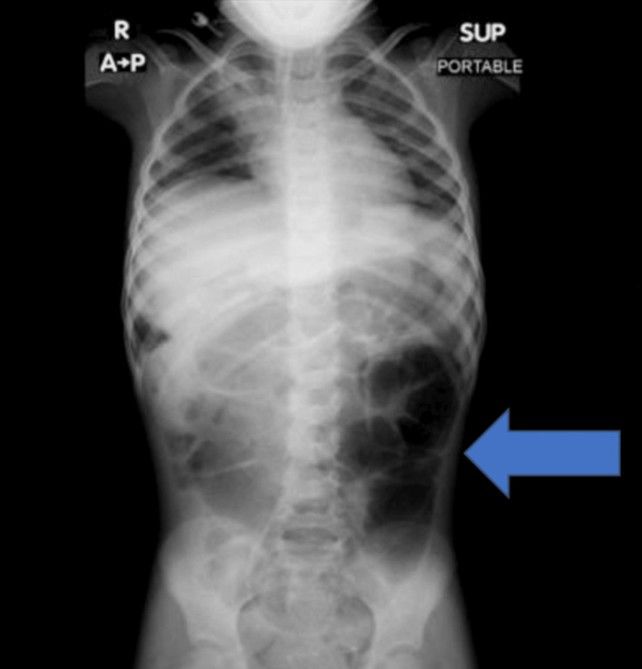

20일 의학 저널 ‘큐레우스(Cureus)’ 실린 보고에 따르면, 사우디아라비아에 거주하는 6세 여자아이는 수주간 이어진 복통과 소화 장애 증상으로 병원을 찾았다. 정밀 검사를 진행한 결과, 의료진은 위 내부에 비정상적으로 큰 이물질이 자리 잡 것을 확인했다.

수술을 통해 제거된 물질의 정체는 다량의 머리카락이 엉켜 형성된 덩어리였다. 해당 덩어리는 위에 머무는 데 그치지 않고 소장 일부까지 길게 이어진 상태였던 것으로 전해졌다.